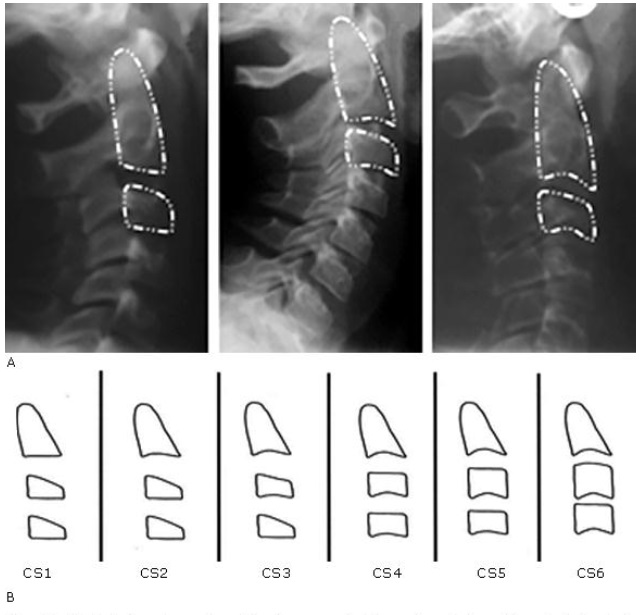

La radiografía lateral de cráneo se solicitó en el protocolo de diagnóstico de ortodoncia y ortopedia maxilar de las clínicas del posgrado de UNICOC, sede Cali. Estas radiografías fueron tomadas en un mismo centro radiológico. Se posicionó la cabeza en el plano de Frankfort paralelo al piso. Además, las radiografías debían involucrar las cuatro primeras vértebras cervicales (C1-C4) (Fig. 1).

A) Estadíos de maduración ósea cervical tomadas de la radiografía lateral de cráneo. B) Esquema representativo donde se identifican los estadios de maduración ósea vertebral cervical bajo los estándares del método descrito por Baccetti y otros.16

La variable estadio de maduración ósea vertebral cervical fue evaluada bajo los estándares del método descrito por Baccetti y otros.10 Este análisis visual se fundamentó en dos características principales:

1. Presencia de concavidad a nivel del borde inferior de los cuerpos de las vértebras cervicales C2, C3 y C4.

2. Forma de los cuerpos de las vértebras cervicales de C3 y C4 (trapezoidal, rectangular horizontal, cuadrada y rectangular vertical).

Estadios de maduración ósea vertebral cervical según Baccetti10 (Fig. 1):

CS1: Todos los bordes inferiores de las vértebras son planos (7 % puede presentar concavidad), C3 y C4 presentan forma trapezoidal. El pico de crecimiento mandibular ocurre 2 años después de este estadio.

CS2: El borde inferior de C2 presenta una concavidad (80 % de los sujetos). C3 y C4 continúan siendo de forma trapezoidal. El pico de crecimiento mandibular inicia 1 año después de este estadio.

CS3: El borde inferior de C2 y C3 presenta concavidad. Los cuerpos de C3 y C4 pueden ser de forma trapezoidal o de forma rectangular horizontal. El pico de crecimiento mandibular inicia en esta etapa.

CS4: Todos los bordes de las vértebras muestran concavidades. C3 y C4 muestran forma rectangular horizontal. El pico de crecimiento mandibular finaliza en esta etapa o ha finalizado un año antes de este estadio.

CS5: Todos los bordes inferiores de las vértebras presentan concavidad. Al menos uno de los cuerpos de C3 o C4 presenta forma cuadrada. Si no es cuadrado el cuerpo de la otra vértebra cervical continúa siendo rectangular horizontal. El pico de crecimiento mandibular ha finalizado 1 año antes de este estadio.

CS6: Todos los cuerpos vertebrales muestran concavidad evidente. Al menos uno de los cuerpos de C3 y C4 muestra forma rectangular vertical. El pico de crecimiento mandibular ha finalizado 2 años antes de este estadio.